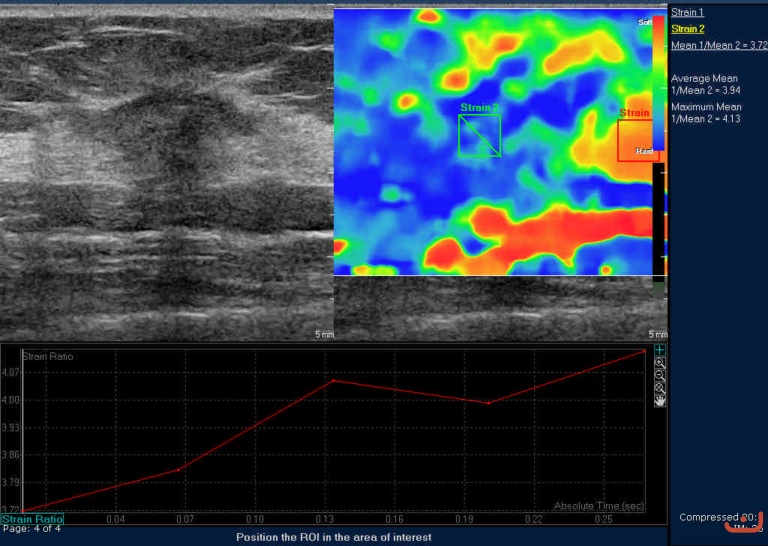

Case 39-E1

Malignant solid mass